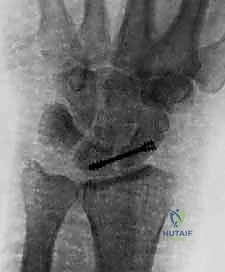

6. إدخال برغي الضغط (Screw Insertion)

يتم قياس طول المسار بدقة متناهية لاختيار البرغي المناسب. يُستخدم برغي ضغط بدون رأس (Headless Compression Screw - مثل برغي هيربرت Herbert Screw). يتم إدخال البرغي فوق السلك الدليلي. تصميم هذا البرغي العبقري (خطوط لولبية مختلفة في طرفيه) يقوم بضغط العظمتين معاً بقوة هائلة أثناء إدخاله، مما يغلق أي فجوة متبقية ويوفر تثبيتاً ميكانيكياً صلباً.